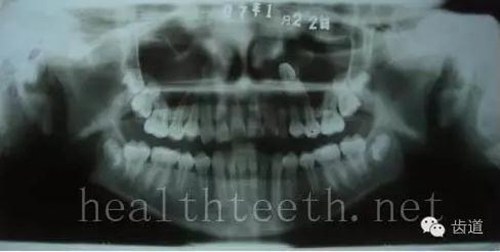

左上乳3滯留,恒3未見萌出,曲面斷層片顯示牙齒埋伏

40.jpg

通過CT片確定埋伏牙齒具體的位置,顯示距離左側(cè)上頜竇很近,偏唇側(cè),這為手術(shù)定位提供了方便